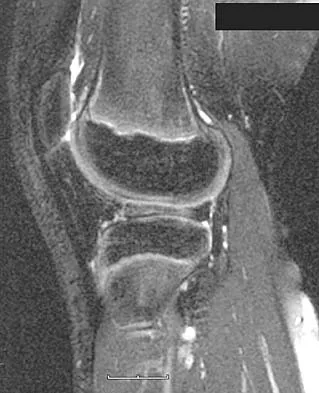

Figures 20a and 20b show the sagittal and coronal T1-weighted MRI scans of a patient's left knee. Abnormal findings include